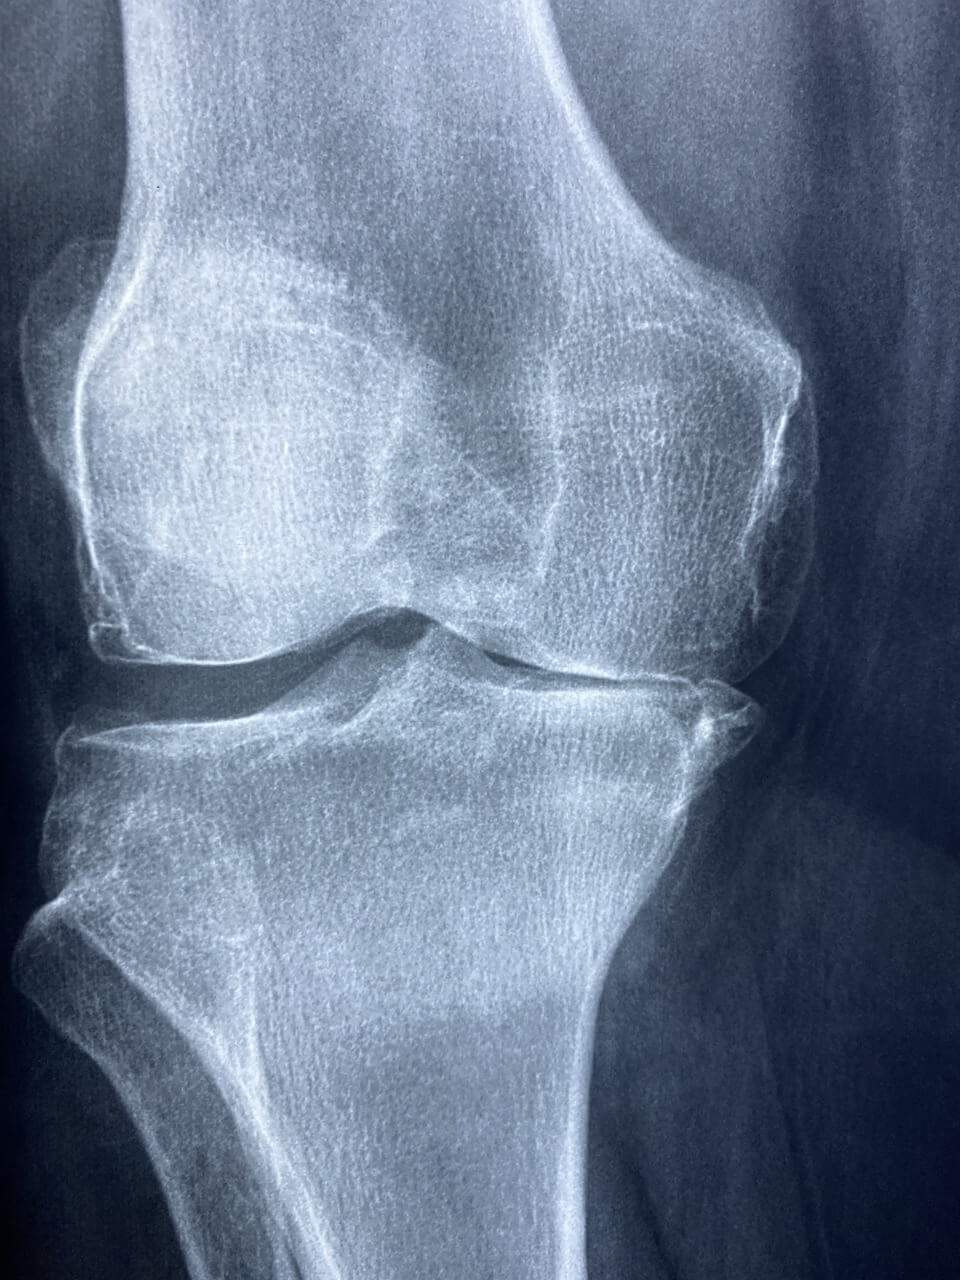

관절 건강은 우리의 일상적인 움직임과 삶의 질에 직결됩니다. 관절 통증이나 불편함은 노화, 과도한 운동, 또는 불균형한 식습관 등 다양한 원인에 의해 발생할 수 있습니다.

이를 예방하고 관리하기 위해 관절 건강에 도움을 주는 관절 영양제를 섭취하는 것이 많은 사람들에게 효과적인 대안으로 여겨지고 있습니다.

이번 글에서는 관절 건강에 유익한 주요 관절 영양제와 그 작용 원리, 올바른 선택 및 섭취 방법, 그리고 관절을 보호하기 위한 생활 습관에 대해 알아보겠습니다.